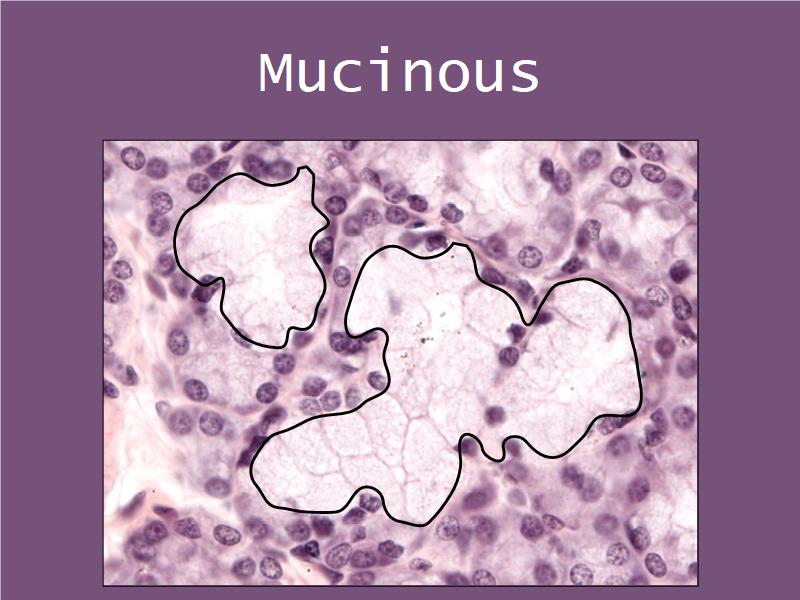

Cancer Association of South Africa (CANSA):Q03 - 1

List 2 types of exocrine secretions:

- Serous

- Mucinous

Mucinous and serous secretory units from the Virtual Microscopy Database at http://virtualmicroscopydatabase.org/

Title: Salivary Gland, Sublingual, Human

Title: Submandibular Gland

Owner: H Goldman

Drexel University - Collection Gastrointestinal System

Used under the BY-SA-NC Creative Commons License